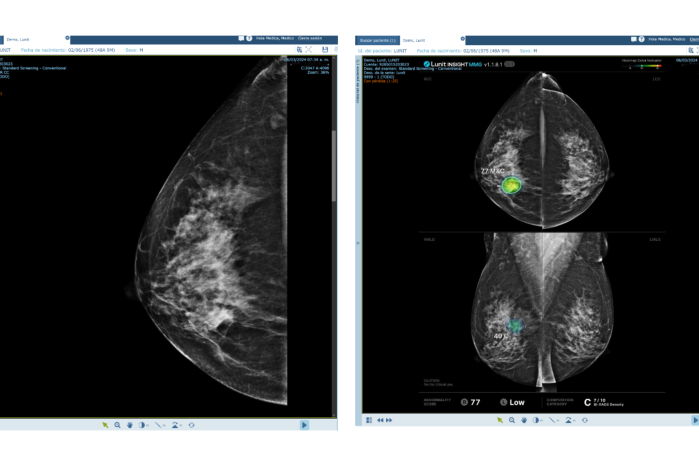

La innovación no se detiene allí. En colaboración con Lunit, líder mundial en inteligencia artificial aplicada a radiología, Maxia ha implementado algoritmos avanzados capaces de detectar tempranamente cáncer de mama y hasta 11 patologías pulmonares. Estos modelos analizan imágenes médicas con una precisión que permite identificar lesiones en sus primeras etapas, cuando los tratamientos son más efectivos y menos invasivos.

- Empodera a los médicos, ofreciéndoles herramientas de apoyo para diagnósticos más rápidos y precisos.

- Optimiza recursos hospitalarios, priorizando casos según su nivel de riesgo.

- Previene complicaciones, facilitando intervenciones tempranas que mejoran el pronóstico y reducen los costos de tratamiento.